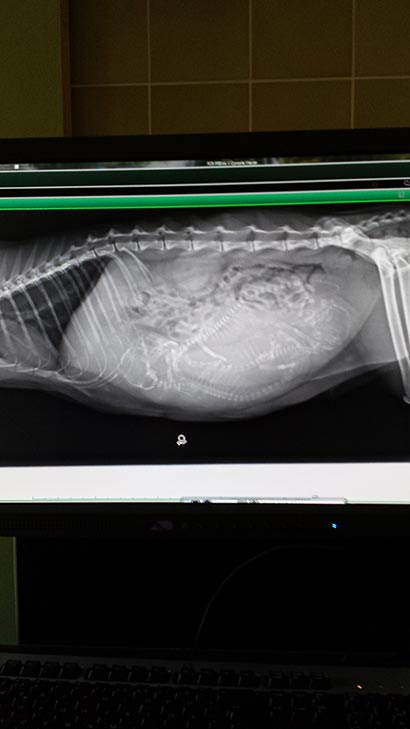

Auf den Röntgenbildern hat man sofort gesehen was los ist. Sie hatte drei Babies.

Da es Ihr immer schlechter ging wurde sie geöffnet, dabei wurde festgestellt das zwei Babies wohl schon länger tot in Ihrem Bauch waren. Ein drittes hat überlebt und wurde zum schöppeln auf eine erfahrene Pflegestelle gebracht.

Hier noch Röntgenbilder: |